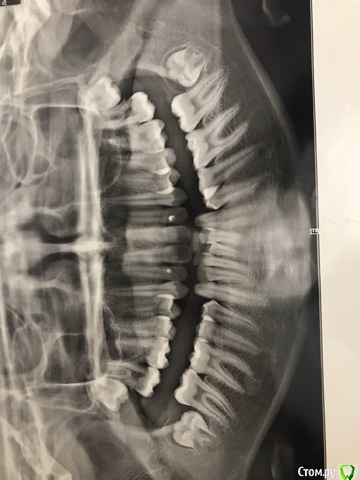

В 15 лет поехали на консультацию в ФГУ ЦНИИСиЧЛХ, диагноз: сочетанная скелетная деформация челюстей, верхняя прогнатия, нижняя ретромикрогнатия, дистальная оклюзия, глубокая резцовая дизокклюзия, сагитальная щель 10 мм, сужение деформация зубоальвеолярных дуг, скученное положение зубов, протрузия резцов, аномалия положения зачатков 8 моляров, уздечки нижней губы, мелкое предверие рта, индивидуальная макродентия.

В Москве на консультации вопрос ортодонтического лечения конкретно не обсуждался, но было рекомендовано 4зуба не удалять, ТК это ухудшит форму лица. Боковые зубы стоят правильно по 1 классу, образовавшаяся щель только из-за положения передних резцов и удлинения альвеолярных дуг. Как вариант, выдвинуть нижную челюсть вперёд аппаратами типа гербста или форсуса.

Брекеты носим два года, прочитав информацию в интернете, понимаю, что у нас прямо взаимоисключающие показатели, предложенное лечение - компромисс. При дефиците места на нижней челюсти лечение без удаления чревато осложнениями.

Через два месяца планируется снятие брекетов. На выходе имеем: профиль лица выпуклый, некрасивый, но по сравнению с тем, что было улучшен. Сагитальная щель 3мм. На нижней челюсти оголились корни передних резцов. Были на консультации у хирургов, назначили день операции по уздечке нижней губы, которая даёт натяжение, но в день операции проводить не стали, сказали - лучше после снятия брекетов, чтобы не травмировать десну перед снятием. Озвучили про подвижность нижних зубов и выход корней из костной ткани. Рекомендовано удаление 8-к.